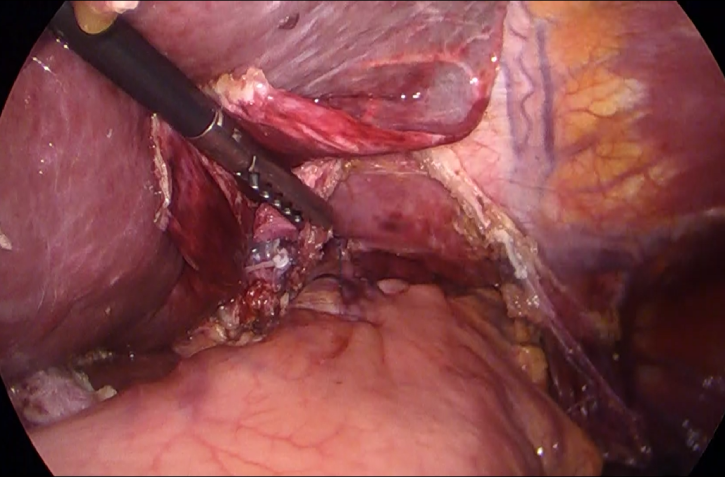

手術による切除

がんのある部位を切除して繋ぐ(吻合)手術です。腹腔鏡手術が主流となっています。昨今では、手術支援ロボットを使用するロボット支援手術(ロボット手術)も実施されています。がんの部位や進行度、浸潤の範囲などにより、様々な術式が用いられますが、がんの根治(がんをとりきる)を前提としたうえで、なるべく患者様の身体に負担が軽い手術が行われます。

術中画像